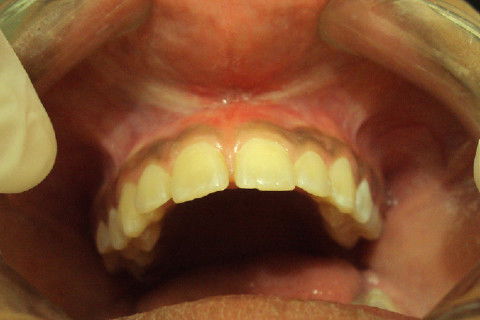

Frontal

Paciente JC, sexo feminino, 13 anos, com uma boa higiene oral, apresentava freio labial superior com insersão muito baixa, ocasionando em diastemas dos incisivos centrais superiores.